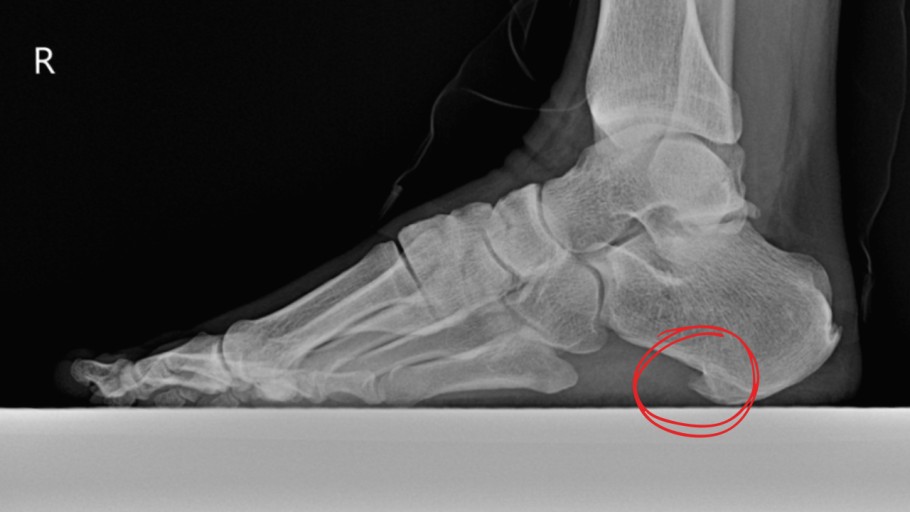

1. 족저근막염 (Plantar Fasciitis)

📌 증상:

- 아침에 일어나 첫발을 디딜 때 발뒤꿈치와 발바닥에 극심한 통증

- 오래 앉아 있다가 일어설 때 통증이 심해지고 움직이면 점차 완화

📌 원인:

족저근막은 발뒤꿈치뼈(종골)에서 시작해 발가락까지 이어지는 강한 섬유 조직인데, 장시간 서 있거나 무리한 운동을 하면 이 조직이 미세하게 찢어지면서 염증이 생깁니다.📌 위험 요인: